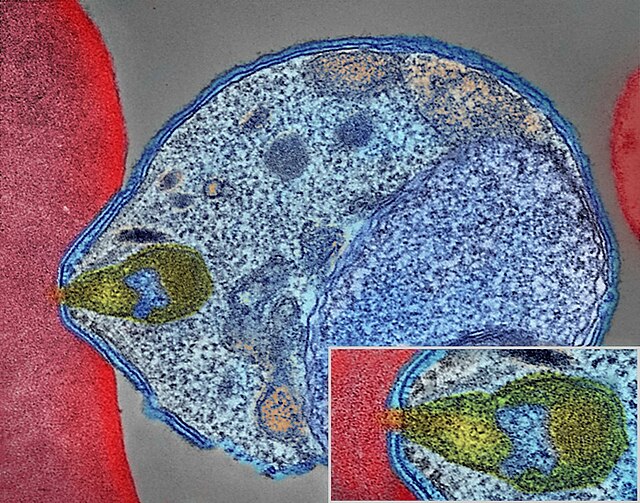

La investigación, publicada en The New England Journal of Medicine, propone una solución poco convencional: convertir a los mosquitos en aliados en lugar de enemigos. Los científicos infectaron mosquitos con una versión modificada genéticamente del Plasmodium falciparum, el parásito responsable de la malaria. Estos parásitos alterados están diseñados para provocar una respuesta inmunitaria en los humanos sin causar la enfermedad.

Para lograr esto, los investigadores crearon dos versiones del parásito:

- GA1, modificado para detener su desarrollo 24 horas después de entrar en el cuerpo humano.

- GA2, diseñado para desarrollarse hasta la etapa hepática, pero sin avanzar más allá.

Estos hallazgos muestran que la versión GA2 del parásito tiene un gran potencial para inducir inmunidad sin causar daño significativo, marcando un avance significativo en la lucha contra la malaria.